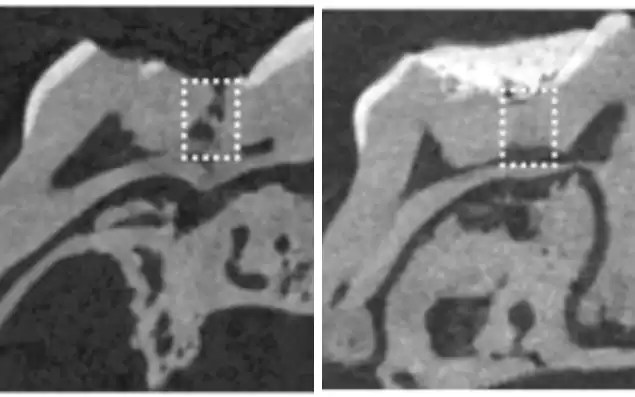

الي اليسار صورة من ثقب في أحد الضروس بعد العلاج لمدة 4 أسابيع والي اليمين صورة لنفس الضرس بعد العلاج لمدة 6 أسابيع

وتوضع إسفنجة مشبعة بالدواء في الثقب ثم توضع طبقة واقية فوق الجزء العلوي، ومع تحلل الإسفنجة حل محلها طبقة من عاج الأسنان كعلاج للأسنان التالفة.

واكتشف العلماء أن العقار الدوائي الذي يطلق عليه “تايدغلوسيب” يعزز نشاط الخلايا الجذعية في لب الأسنان على نحو أمكنه إصلاح ثقوب بقدر 0.13 ميلليمتر في أسنان الفئران.